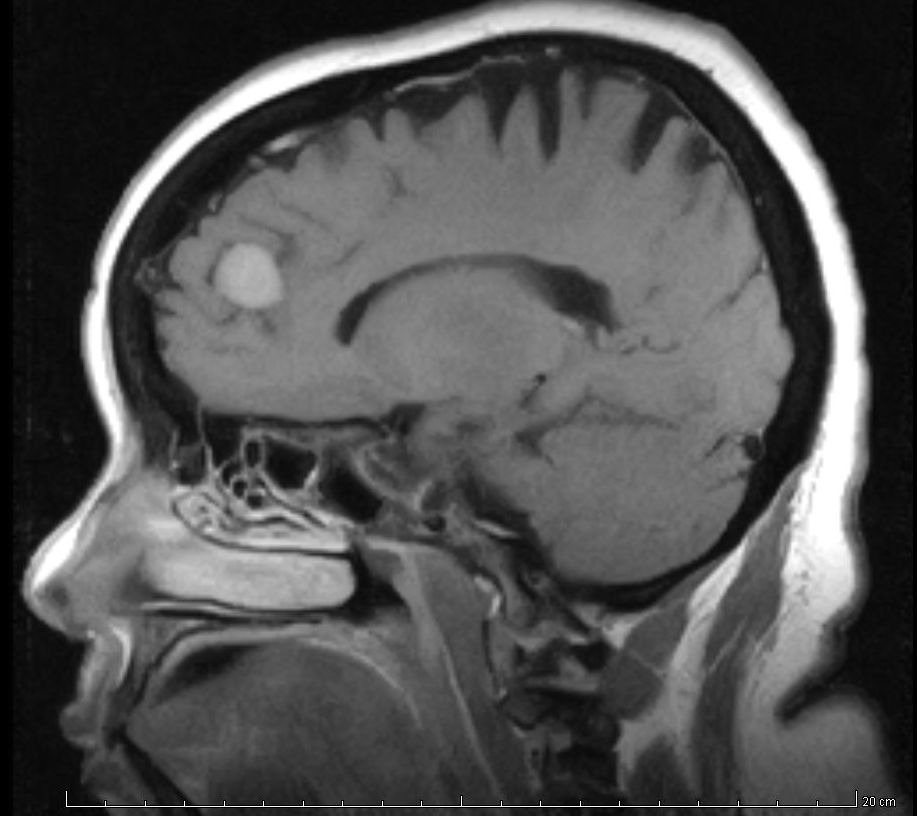

Hallazgos incidentales en resonancia magnética

26 noviembre 2018

Se revisa la frecuencia y la gravedad de los hallazgos inesperados en resonancias de cerebro, tórax y abdomen. British Medical Journal, 22 de noviembre de 2018